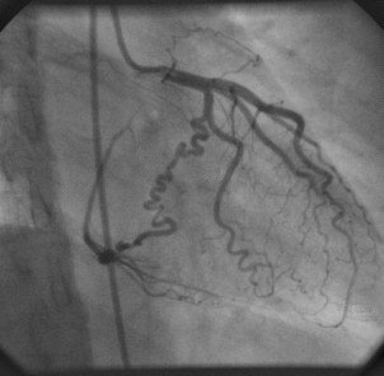

This coronary angiogram view from a left heart catheterization clearly shows the entire circumflex artery and OM branches

What is RAO caudal?